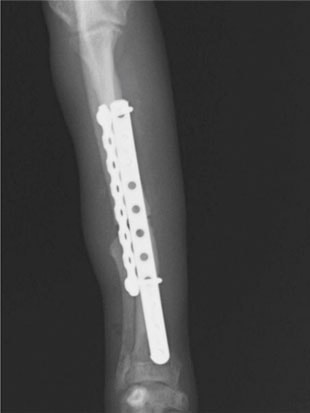

トイプードル 右遠位橈尺骨短斜骨折のALPSによる内固定